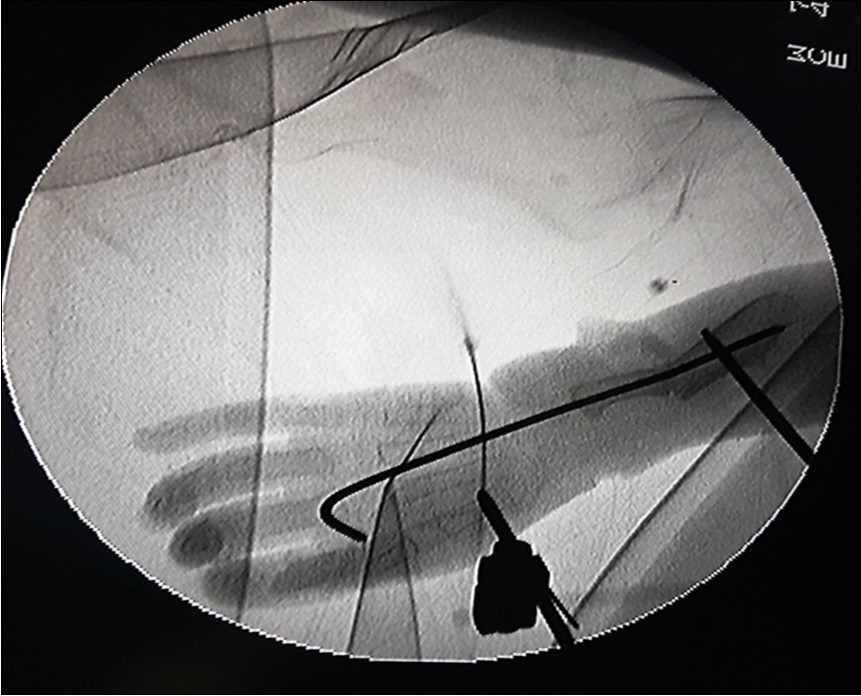

The ulnar osteotomy was stabilised with an intramedullary 2.0mm Kirchner wire (K-wire). Wrist bridging external fixators were mounted bilaterally to maintain correction until 12 weeks after surgery. Intraoperative fluoroscopic image of the correction of the left forearm is depicted in figure 3.

Figure 3.Fluoroscopic image showing the K-wire running from the 3rd metacarpal to bridge the ulnar osteotomy. The Schanze screws of the external fixator are shown, one each in the first metacarpal and in the proximal ulna with the forearm in pronation.